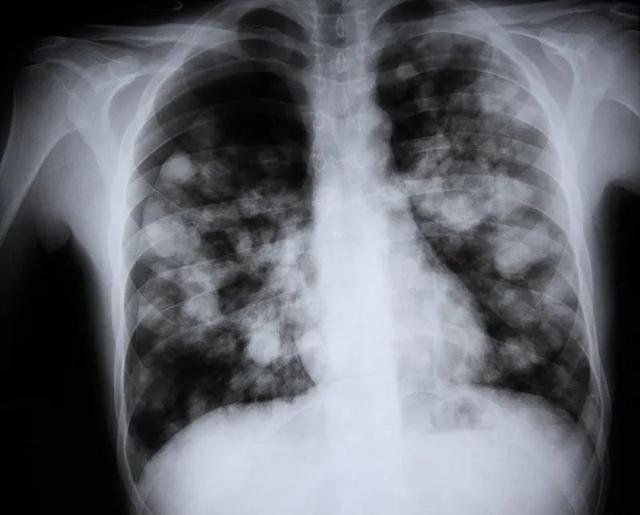

陆主任在仔细分析病情和影像学检查后,高度怀疑朱先生可能合并侵袭性肺曲霉病感染,立即安排行床旁纤维支气管镜检查及肺泡灌洗液查病原体,终于揪出“真凶”——流感相关性肺曲霉病(IAPA),随后立刻针对该患者调整治疗方案,启动抗霉菌治疗。